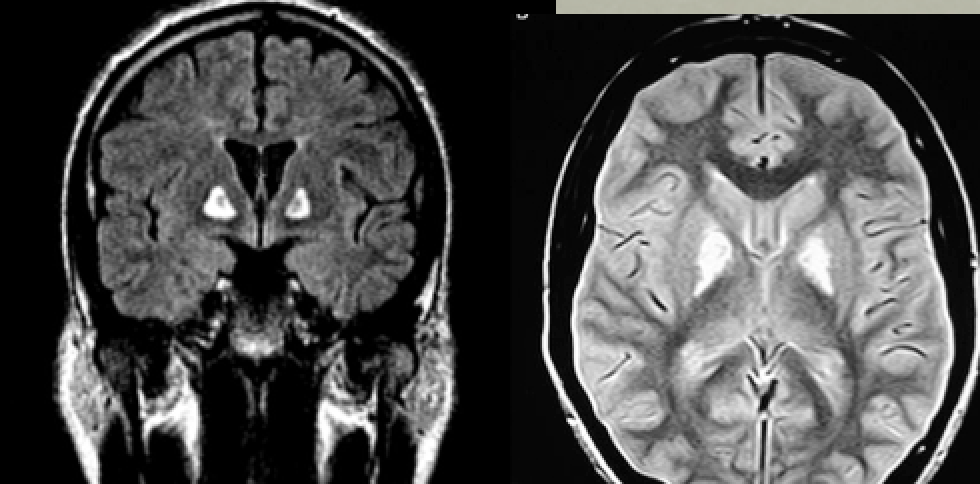

65yo man found dead in bed, wife attempts to cash in new $1 million life insurance policy hours later

Likely diagnosis?

Other considerations?

Carbon monoxide poisoning

CT: hypodense basal gangila (especially globus pallidus)

MRI: T2 bright basal ganglia, especially globus pallidus, can restrict diffusion acutely

(note also diffusely T2 dark white matter, another CO feature)

Other differential diagnoses: Cyanide poisoning (globus pallidus)

methanol toxicity or Wilson’s disease (but generally involve putamen)

(thanks to Raf Llinas)